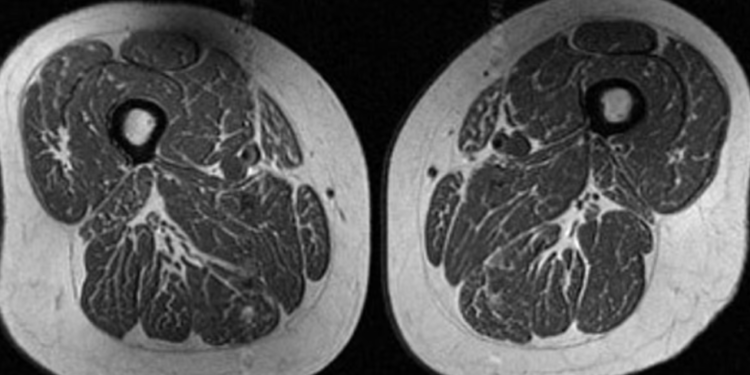

Imazhi duket si një copë mishi shumë e “mermerizuar”, që të kujton një biftek me shumë fijëza yndyre të shpërndara imët. Por kjo nuk është darkë. Është një skanim MRI i kofshës së një gruaje 62-vjeçare që merrte 87% të kalorive të saj vjetore nga ushqime ultra të përpunuara.

“Kjo pjesëmarrëse ushqehej kryesisht me drithëra të ftohta, çokollata ose karamele, pije të gazuara të zakonshme ose pije të ëmbla në shishe,” tha Dr. Zehra Akkaya, studiuese dhe konsulente në grupin e kërkimit për imazherinë muskuloskeletore në Universitetin e Kalifornisë, San Francisko.

Vijat e fshehura të yndyrës mes dhe brenda fibrave muskulore mund të sinjalizojnë probleme serioze shëndetësore, tha Akkaya, autorja kryesore e një studimi të ri që analizoi si ndikojnë ushqimet ultra të përpunuara në yndyrën brenda muskujve tek njerëzit në rrezik për osteoartrit të gjurit. Ushqimet ultra të përpunuara janë lidhur me shtim në peshë dhe obezitet, si dhe me zhvillimin e sëmundjeve kronike si kanceri, sëmundjet kardiovaskulare, diabeti i tipit 2 dhe depresioni. Këto ushqime mund të shkurtojnë edhe jetën.

Një grua tjetër 61-vjeçare në studim kishte gjithashtu yndyrë të shpërndarë në muskujt e kofshës, por jo aq të theksuar. Rreth 29% e dietës së saj përbëhej nga ushqime ultra të përpunuara.

“Ishte veçanërisht shqetësuese sepse këta individë, të skanuar në një kohë kur nuk kishin shenja të osteoartritit të gjurit tashmë tregonin cilësi të dobësuar të muskujve,” tha Akkaya.